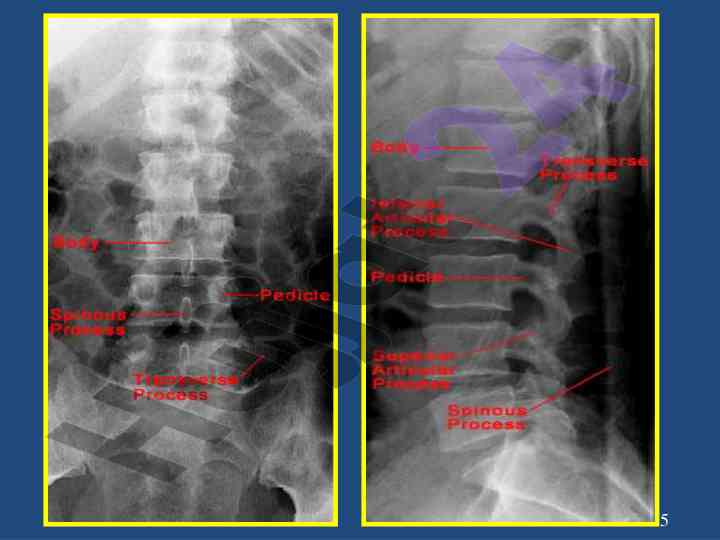

Umurtqa o‘ta og‘ir va jiddiy jarohatlari va ularning davolash usullari haqida ilmiy maqola. Kompressiya sinishi va uning röntgenologik ko‘rinishlari keltirilgan.